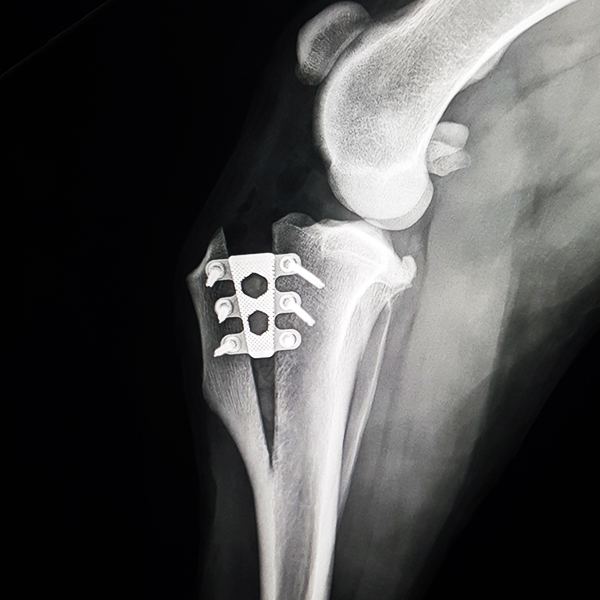

Case Overview In November 2025, Skeeter, a 14-week-old Doodle puppy weighing ...

Pioneering Small PatientOrthopedics with the 1.5 mmLeiLOX TPLO Swing Titanium Plate ...